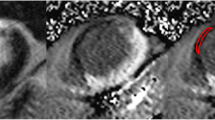

On a segmental basis, STIR differentiated acute from chronic infarcts with a sensitivity of 95% by both methods and a specificity of 99% by visual assessment and 97% by semi-quantitative assessment. On the STIR images at six months, by visual assessment, three patients had STIR segments exhibiting hyper-intensity; by semi-quantitative assessment, four patients had STIR positive segments. In the three patients with persistent hyper-intensity on visual assessment, the hyperintense segments correlated with infarcted segments, and had been hyperintense at the acute stage. Potential reasons for persistent myocardial oedema could include increased wall stress and/or residual/recurring ischemia, alterations in drainage of the infarcted segments as a result of vessel damage or continuing tissue repair. In all cases the number of hyperintense segments was less than at the acute stage (Figure 4). In the one remaining patient, semi-quantitative assessment identified the septum as having a higher signal, a false positive finding not seen on visual assessment.

Example of persistent hyperintense signal on STIR at 6-month follow-up. Matched diastolic images obtained in a 76-year-old male with reperfused inferior MI. The acute images demonstrate a large area at risk on STIR (A) with a smaller infarcted zone (B). The images at 6 months show the infarct zone has has become slightly larger (D), whereas the STIR images (C) show near homogenous signal distribution but a small remaining area of hyperintensity.